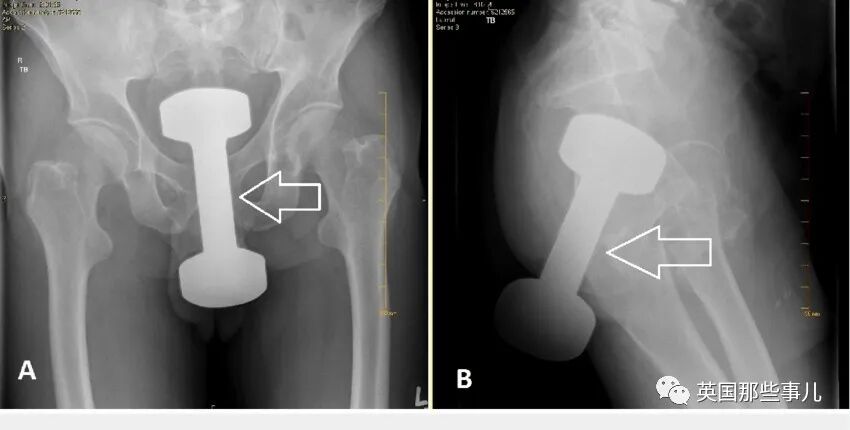

X光片显示,可以明显看到,

一个近20厘米长的哑铃,卡在结肠与直肠的交汇处。

起初医生尝试用手术镊子等工具,但迟迟无法取出哑铃。

医生只好自己“手动移除”,将前臂的一部分伸进去,才成功取出这个哑铃。

据悉,这个哑铃长达20厘米,重量达到2公斤。